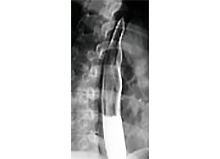

PCI実施後に血行再建された冠動脈

冠動脈は心臓に酸素を送るための重要な血管です。しかし、心筋梗塞や狭心症になるとこの血管が狭くなってしまいます。これを調べるために心臓内にカテーテルを挿入して冠動脈の様子を観察します。次に治療ですが、カテーテルを通して、細くなった冠動脈を風船で膨らませる経皮的冠動脈形成術(PCI)が行われています。一般に風船治療と言われていますが、患者さんの苦痛も少なく非常に有効な治療法で、ここ数年、日本を含め世界的に多数行われています。